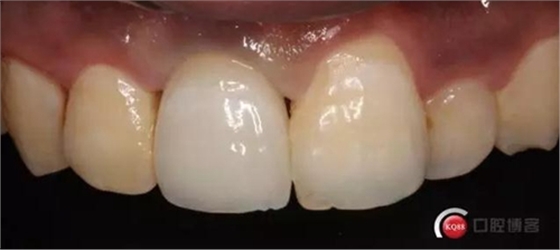

可以看出牙齦袖口很漂亮,修復(fù)體外形也不錯(cuò),就是顏色偏白一點(diǎn),讓患者改色,患者覺得已經(jīng)很滿意了,而且考慮其他牙以后做美白,所以不換了。

可以看出修復(fù)體的邊緣密合度都很好。希望這次修復(fù)能夠讓這顆牙多服役幾年吧